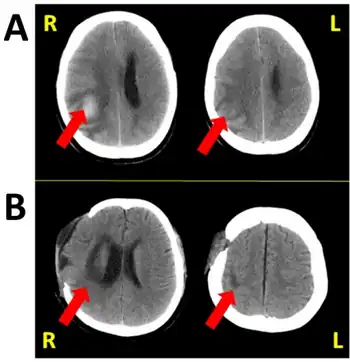

Hemispatial neglect results most commonly from strokes and brain unilateral injury to the right cerebral hemisphere, with rates in the critical stage of up to 80% causing visual neglect of the left-hand side of space. Neglect is often produced by massive strokes in the middle cerebral artery region and is variegated, so that most sufferers do not exhibit all of the syndrome's traits.[4] Right-sided spatial neglect is rare because there is redundant processing of the right space by both the left and right cerebral hemispheres, whereas in most left-dominant brains the left space is only processed by the right cerebral hemisphere. Although it most strikingly affects visual perception ('visual neglect'), neglect in other forms of perception can also be found, either alone or in combination with visual neglect.[5]

For example, a stroke affecting the right parietal lobe of the brain can lead to neglect for the left side of the visual field, causing a patient with neglect to behave as if the left side of sensory space is nonexistent (although they can still turn left). In an extreme case, a patient with neglect might fail to eat the food on the left half of their plate, even though they complain of being hungry. If someone with neglect is asked to draw a clock, their drawing might show only the numbers 12 to 6, or all 12 numbers might be on one half of the clock face with the other half distorted or blank. Neglect patients may also ignore the contralesional side of their body; for instance, they might only shave, or apply make-up to, the non-neglected side. These patients may frequently collide with objects or structures such as door frames on the side being neglected.[1]

Brain areas in the parietal and frontal lobes are associated with the deployment of attention (internally, or through eye movements, head turns or limb reaches) into contralateral space. Neglect is most closely related to damage to the temporo-parietal junction and posterior parietal cortex.[7] The lack of attention to the left side of space can manifest in the visual, auditory, proprioceptive, and olfactory domains. Although hemispatial neglect often manifests as a sensory deficit (and is frequently co-morbid with sensory deficit), it is essentially a failure to pay sufficient attention to sensory input.

Although hemispatial neglect has been identified following left hemisphere damage (resulting in the neglect of the right side of space), it is most common after damage to the right hemisphere.[8] This disparity is thought to reflect the fact that the right hemisphere of the brain is specialized for spatial perception and memory, whereas the left hemisphere is specialized for language - there is redundant processing of the right visual fields by both hemispheres. Hence the right hemisphere is able to compensate for the loss of left hemisphere function, but not vice versa.[9] Neglect is not to be confused with hemianopsia. Hemianopsia arises from damage to the primary visual pathways cutting off the input to the cerebral hemispheres from the retinas. Neglect is damage to the processing areas. The cerebral hemispheres receive the input, but there is an error in the processing that is not well understood.